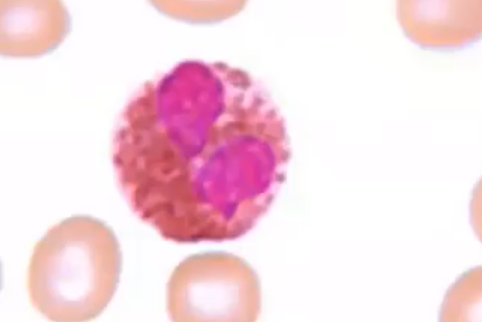

Name

Monocyte

largest WBC

larger molecule phagocytic

Pacman